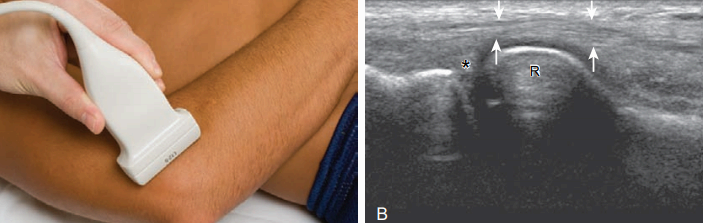

뒤쪽검사(posterior) 팔꿈치의 뒤쪽 구조물을 검사하려면 환자의 팔꿈치를 굽혀야 한다. 누운 자세에서 환자의 손을 배 위에 가로 방향으로 놓는다. 검사할 중요 구조물들은 뒤쪽관절오목, 위팔세갈래근, 팔꿈치머리 부위의 연조직(soft tissue)이다.

몸 쪽 팔꿈치 뒤쪽에서 탐촉자를 시상면으로 놓으면 위팔뼈가 높은 에코와 소리그림자의 특징적인 뼈 윤곽으로 보인다. 위팔뼈 몸통에서 팔꿈치관절 쪽으로 이동하면 팔꿈치오목이 뚜렷하게 보이며, 가로면 영상에서도 확인할 수 있다. 이 오목은 정상적으로 높은 에코의 뒤쪽 팔꿈치 지방덩이로 채워져 있으며 관절액과 관절내소체(intra-articular bodies)의 검사 또한 이 부위에서 시행한다. 높은 에코의 도더래와 작은 머리 유리연골도 확인할 수 있다. 팔꿈치오목의 표층에서는 낮은 에코의 위 팔세 갈래근이 보이고 아래쪽으로는 높은 에코의 힘줄이 팔꿈치돌기에 부착되는 것을 볼 수 있다. 팔꿈치를 펴면 팔꿈치돌기의 표층 연조직 부위에서 팔꿈치윤활주머니 액을 검사할 수 있다. 팔꿈치윤활주머니 액을 검사할 때는 탐촉자를 두꺼운 겔(gel) 층 위에 압력에 의해 소량의 액이 눌려 보이지 않을 수 있기 때문이다. 앞서 언급한 구조물들을 검사할 때에는 시상면 영상이 가장 중요하지만 가로면 영상 또한 해부학적 구조물과 특징적인 병적 소견을 확인하는 데 있어 도움이 된다.